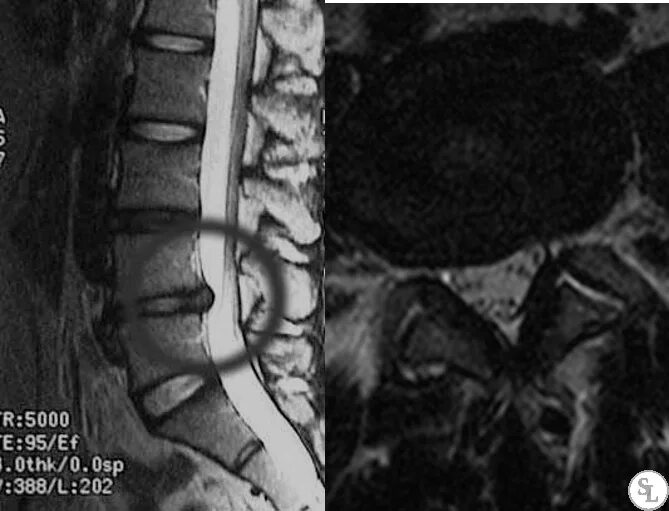

Грыжа диска l4 l5